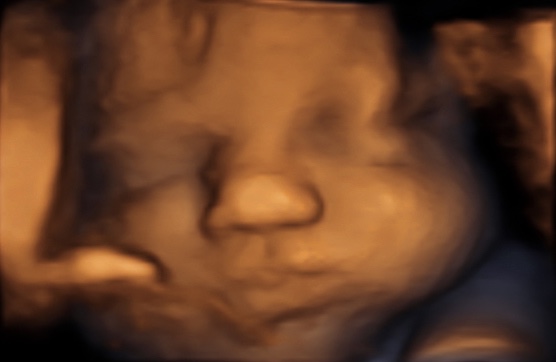

37 weken

Een echo na 37 weken.